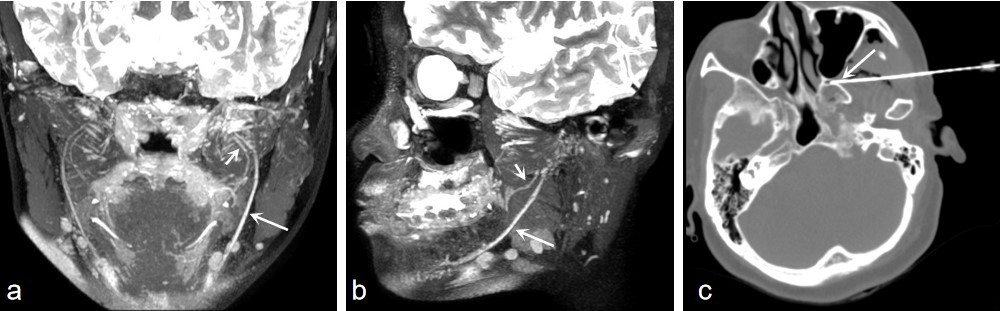

(2)三叉神经痛MRI诊断及介入微创治疗

43岁女性患者,左三叉神经下颌支支配区疼痛,VAS为8分。A,B 3D T2WI-CUBE fs重建图像显示,左三叉神经分支的下颌支的舌神经(短箭头)和下牙槽神经分支(长箭头)较右侧增粗,信号增高。 CCT图像显示蝶腭神经节阻滞。 治疗后,患者疼痛程度明显减轻,VAS评分降至2分。